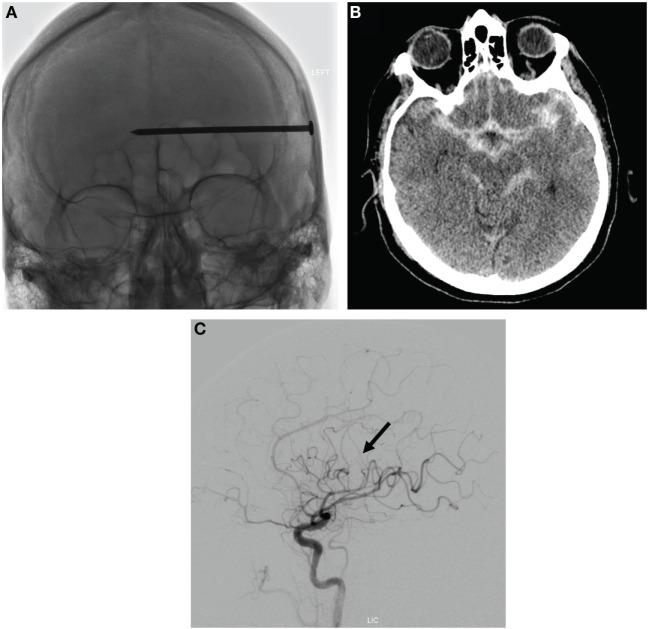

Penetrating brain trauma commonly results in occult neurovascular injury. Detailed cerebrovascular imaging can evaluate the relationship of intracranial foreign bodies to major vascular structures, assess for traumatic pseudoaneurysms, and ensure hemostasis during surgical removal. We report a case of a self-inflicted intracranial nail gun injury causing a communicating ventricular tract hemorrhage upon removal, as well as a delayed pseudoaneurysm. Pre- and post-operative vascular imaging, as well as intra-operative endovascular assistance, was critical to successful foreign body removal in this patient. This report demonstrates the utility of endovascular techniques for the assessment and treatment of occult cerebrovascular injuries from intracranial foreign bodies.

穿透性脑外伤常导致隐匿性神经血管损伤。详细的脑血管成像可评估颅内异物与主要血管结构的关系,检测创伤性假性动脉瘤,并确保手术取出异物时的止血效果。我们报告一例自伤性颅内钉枪伤病例,取出异物时导致交通性脑室系统出血以及迟发性假性动脉瘤。术前和术后血管成像以及术中血管内辅助对该患者成功取出异物至关重要。本报告证明了血管内技术在评估和治疗颅内异物所致隐匿性脑血管损伤中的作用。